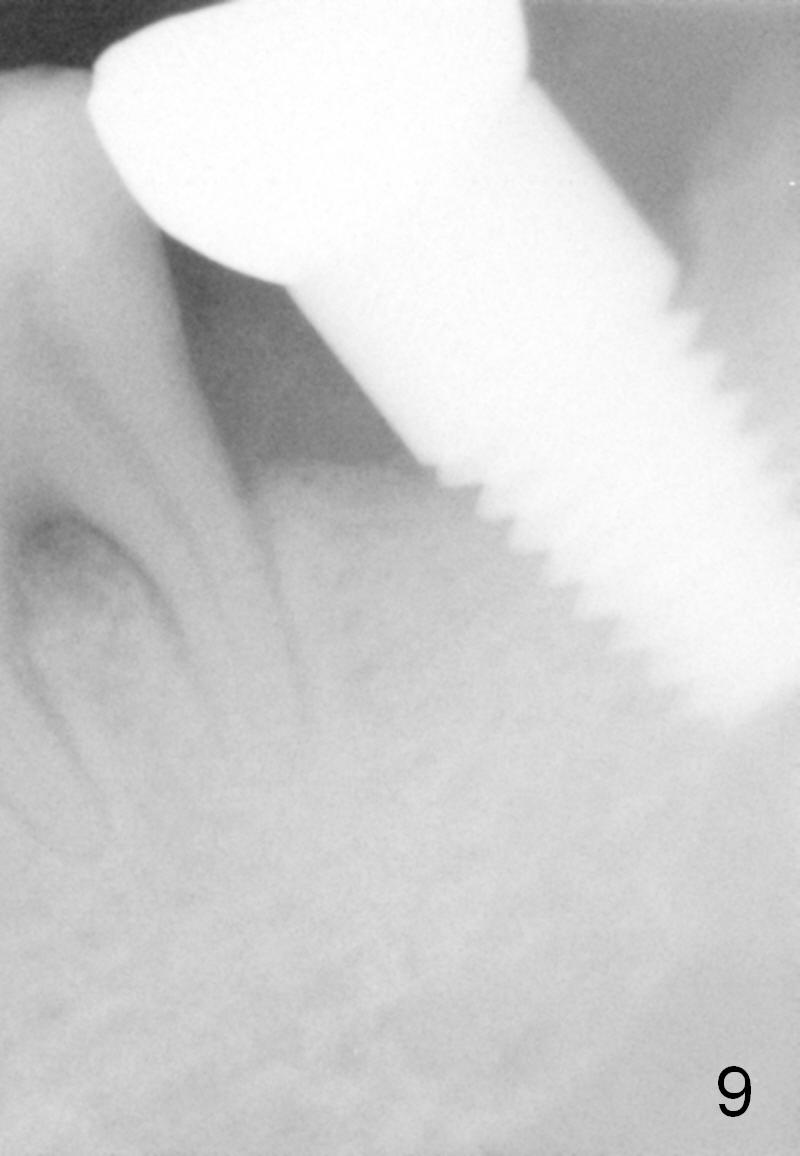

There is no bone resorption 6 months post cementation (12 months postop, Fig.8,9). Mild bone resorption is observed 3 years post cementation (Fig.10). It may be related to the large implant (7 mm) in association with chronic periodontitis and bruxism. The roots of the teeth #19 and 30 fracture 6 years 5 months post cementation at #18 (Fig.11). Since gingival recession is severe at #18 probably related to the large implant, the one at #19 will be designed small.